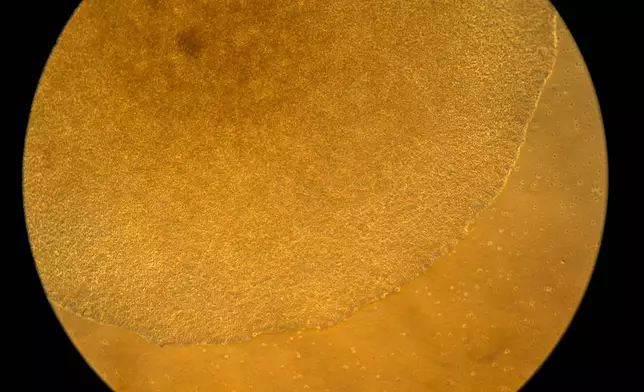

Research fellow Sachin Surwase shows an image of a pancreatic lymph node from a mouse in the lab where he studies autoimmune diseases at Johns Hopkins University in Baltimore, Md., Tuesday, May 13, 2025. (AP Photo/David Goldman)

Human stem cells used in research into autoimmune diseases are visible under a microscope in a lab at the National Institutes of Health, Monday, Aug. 25, 2025, in Bethesda, Md. (AP Photo/David Goldman)